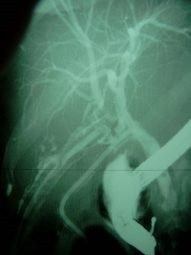

Lesión de conducto hepático derecho post colecistectomía

Envíado por Dr. Carlos Miguel Zavaleta Consuegra